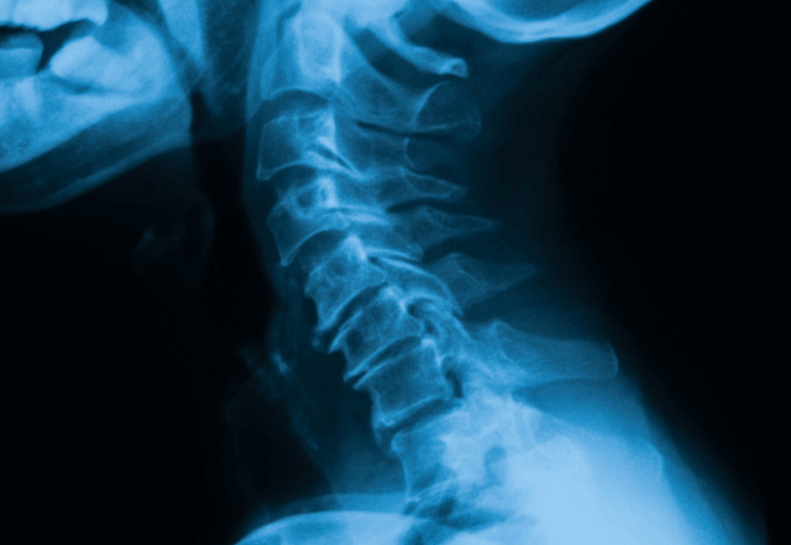

Lordoza Cervikale dhe Fizioterapia

Lordoza cervikale është harku natyral i shtyllës kurrizore në qafë. Në raste të caktuara, ky hark mund të humbasë formën e tij normale (drejtim ose shtrembërim), duke shkaktuar dhimbje dhe kufizim të lëvizjes. Ky problem lidhet shpesh me qëndrime të gabuara, punë të gjata para kompjuterit, trauma ose degjenerim të disqeve ndërvertebrale.